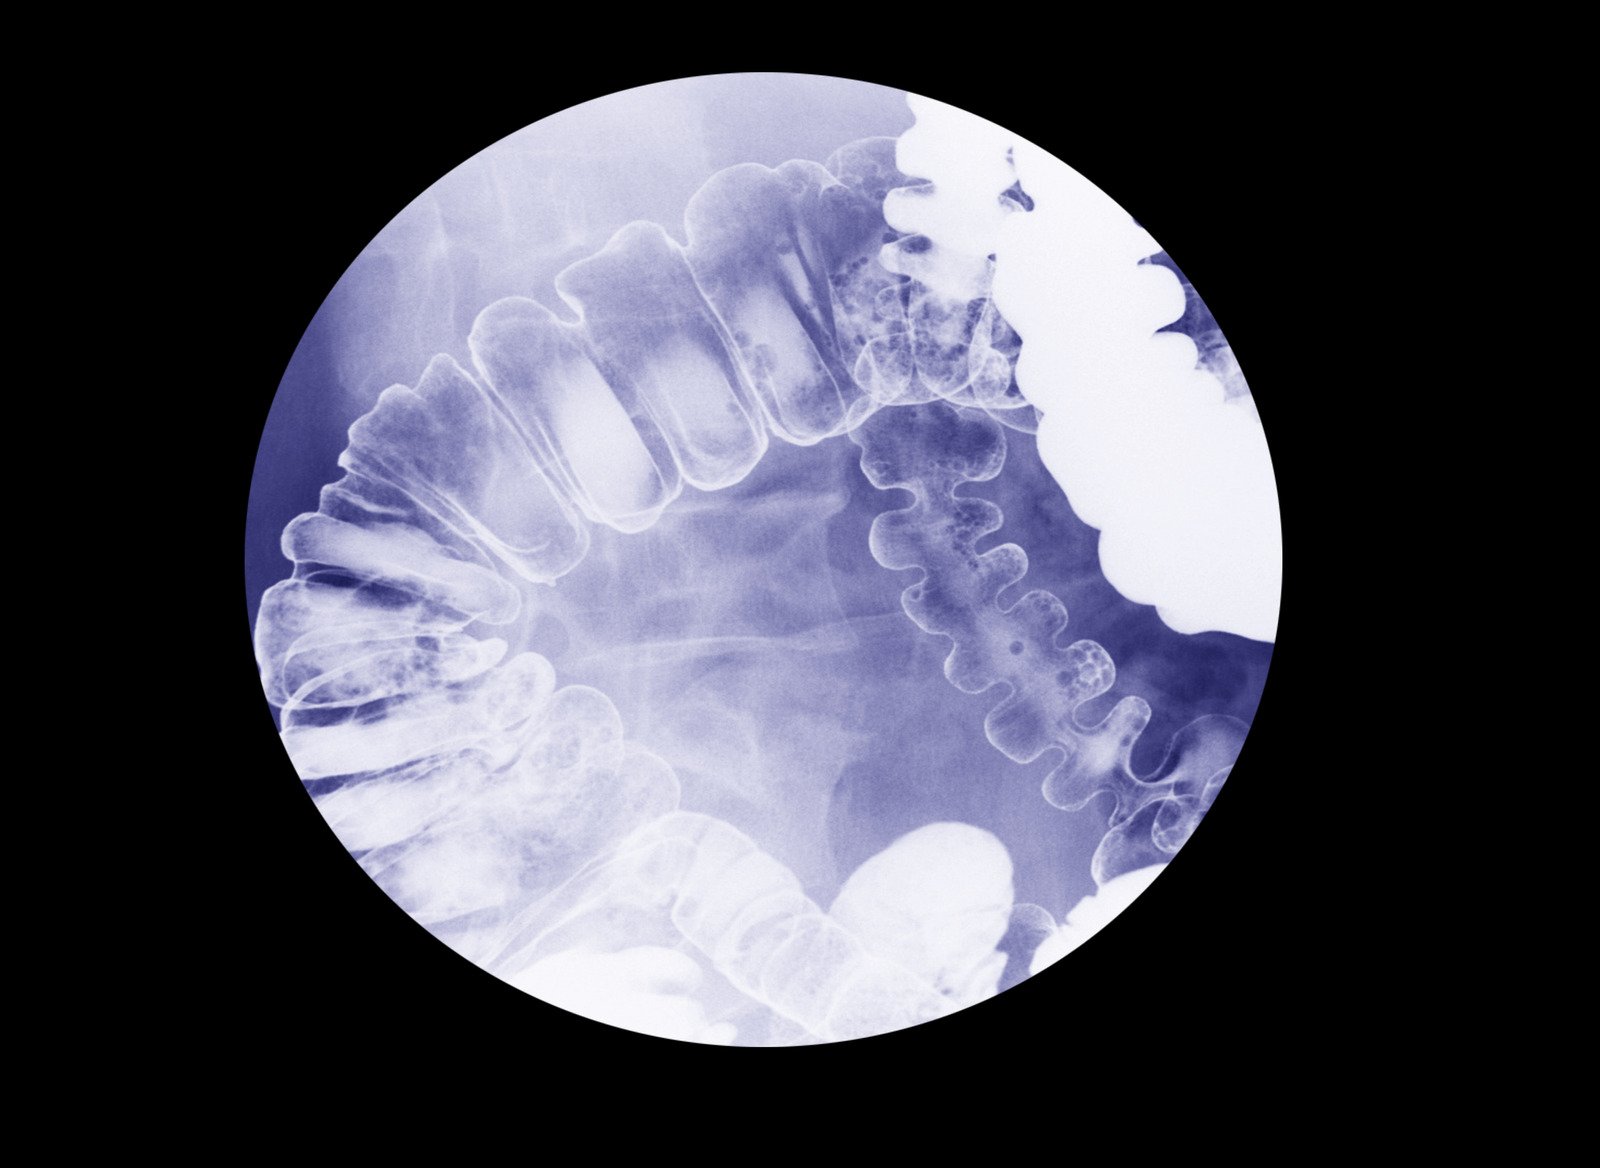

바륨 조영술은 식도와 위의 구조적 이상을 진단하기 위해 바륨을 이용하여 X선 촬영을 하는 검사입니다.

바륨은 X선에서 뚜렷하게 보이는 성질이 있어 식도와 위의 내부 구조를 선명하게 보여줍니다.

바륨 조영술은 바륨 현탁액을 마신 후 X선을 촬영하여 식도, 위, 십이지장의 형태와 기능을 평가하는 검사입니다.

바륨은 밀도가 높아 X선에서 흰색으로 나타나므로 내부 장기의 윤곽과 이상 유무를 정확하게 파악할 수 있습니다.